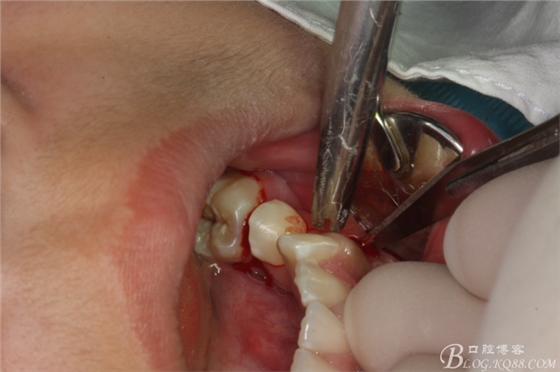

圖3. 34頰側(cè)垂直切口加36齦溝內(nèi)水平切口。